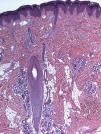

HistopatologíaEl estudio histológico de una biopsia en sacabocados de 4mm obtenida del centro de la lesión mostraba una proliferación de vasos dilatados con paredes finas en la dermis superficial y profunda, íntimamente asociados a un número aumentado de glándulas ecrinas de tamaño y morfología normal, algunos folículos pilosos y tejido adiposo. No se observaban cambios epidérmicos, figuras mitóticas ni atipia citológica (figs. 2 y 3).

Los hallazgos histopatológicos incluyen un número aumentado de estructuras ecrinas en la dermis media y baja, adyacente a racimos de vasos dilatados, generalmente de naturaleza capilar. Las estructuras ecrinas están bien diferenciadas, pero pueden estar aumentadas de tamaño. También se ha descrito la presencia de focos grasos en la dermis, folículos pilosos, haces nerviosos hiperplásicos, vasos linfáticos o mucina. Ocasionalmente pueden hallarse cambios epidérmicos que incluyen hiperplasia epidérmica, papilomatosis e hiperqueratosis1–5.